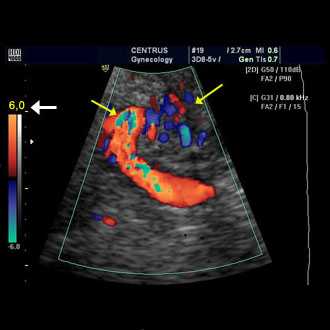

Doppler ultrasound is a special ultrasound technique that evaluates blood as it flows through a blood vessel, including the body's major arteries and veins in the abdomen, arms, legs and neck.

In an ultrasound examination, a transducer both sends the sound waves into the body and receives the echoing waves. ... Doppler ultrasound, a special application of ultrasound, measures the direction and speed of blood cells as they move through vessels.